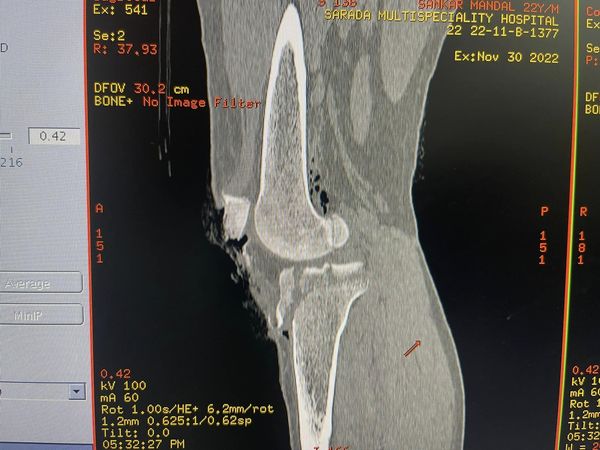

A 22-year-old western dance and music teacher with an open fracture of the distal femur, and proximal tibia, a large chunk of patella lost on the street, and a patellar tendon torn and tattered with a grossly contaminated wound filled with debris and paint flakes from his bike. This is the sort of thing that is mainly treated with prayers (classic Bollywood style “dawa nehi dua ki zaroorat”) however the closest 2nd most effective thing is ilizarov. These are versatile ringfixators that take care of such extensive injuries while giving the soft tissue and skin a fighting chance to be repaired and healed.